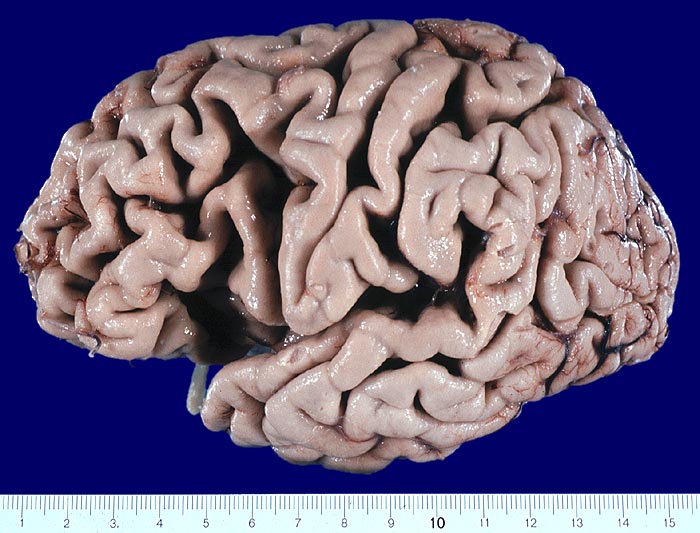

Gehirne von Alzheimer Patienten sind makroskopisch durch eine kortikale Atrophie (vor allem temporo-parietal) charakterisiert. Weiter findet sich meist eine deutliche Atrophie von Hippocampi und Mandelkernen. Diese geht einher mit einem Hydrocephalus internus (e vacuo), wobei vor allem die Temporalhörner der Seitenventrikel betroffen sind.